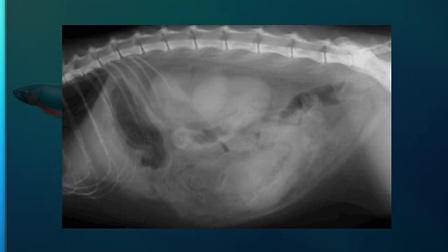

我们重点谈谈X光在医学领域的应用,在医疗领域,X光技术已经发展成为一个庞大的体系,包括X光透视、X光摄影等,X光透视是一种非常常见的检查方法,广泛应用于骨科、呼吸科等多个领域,通过X光透视,医生可以清晰地观察到人体内部的结构,如骨骼、肺部等,这对于疾病的早期发现和治疗具有非常重要的意义,X光摄影更是帮助我们了解人体内部结构的重要手段,当我们因为骨折或其他疾病需要了解骨骼情况时,医生通常会通过X光摄影来获取清晰的图像,从而帮助我们制定治疗方案。